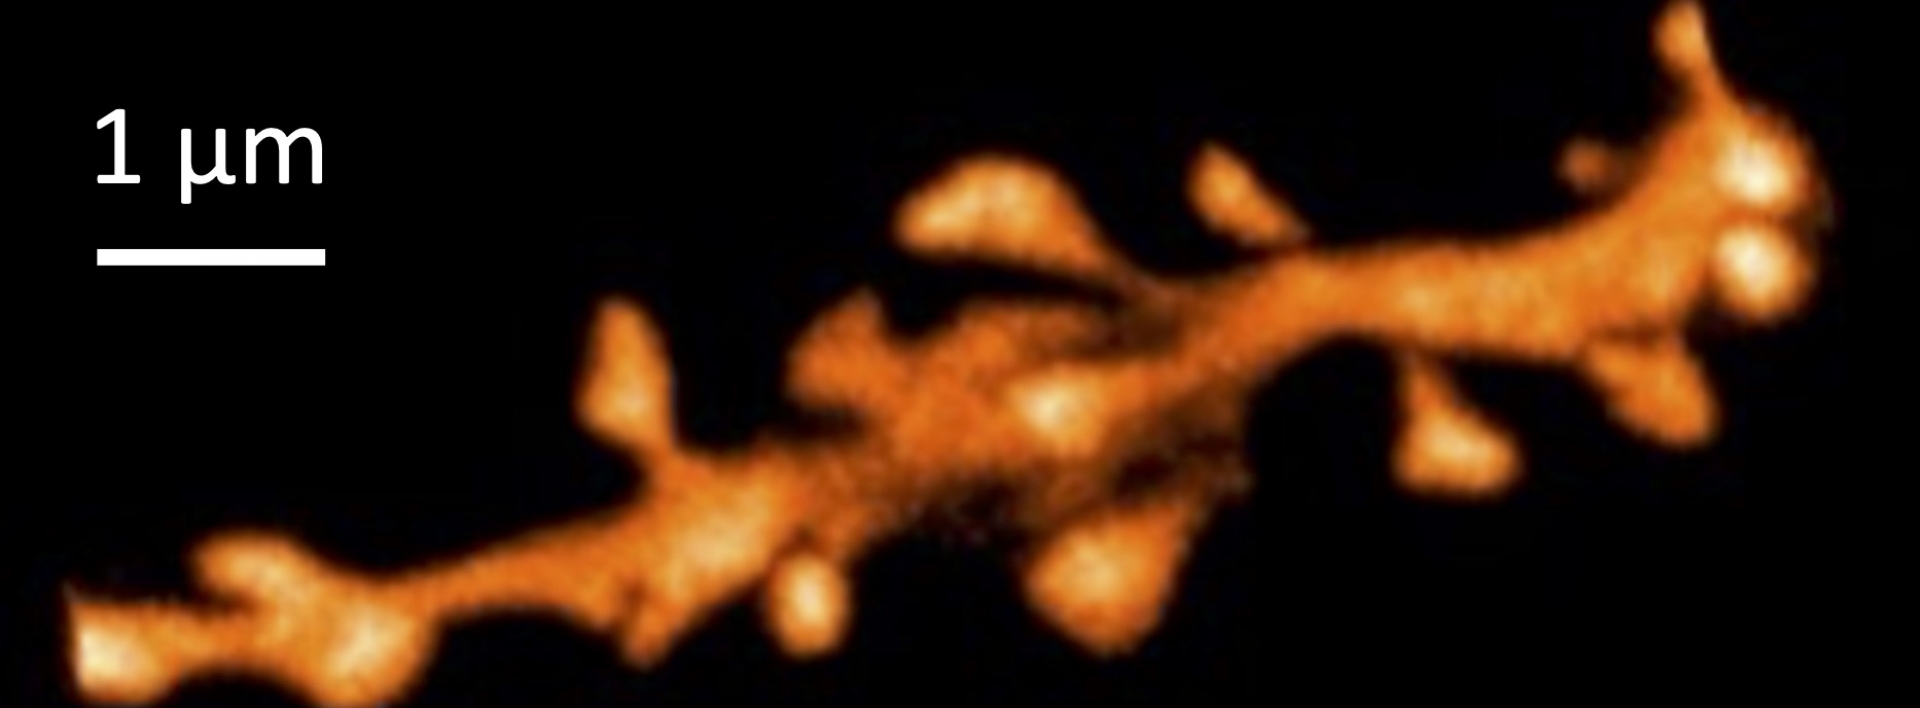

Nous recherchons, en manipulant pharmacologiquement la HSP, à élucider la relation entre la taille de la PSD, la perte synaptique et la fonction neuronale dans un modèle murin de maladie d’Alzheimer, à l’aide de techniques fonctionnelles (électrophysiologie) et structurelles (marquages immunofluorescents de la PSD, des épines dendritiques et des versants pré et post-synaptiques à l’aide de la microscopie super-résolutive STED).